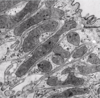

microvilli

absorption (microvilli seen by EM)